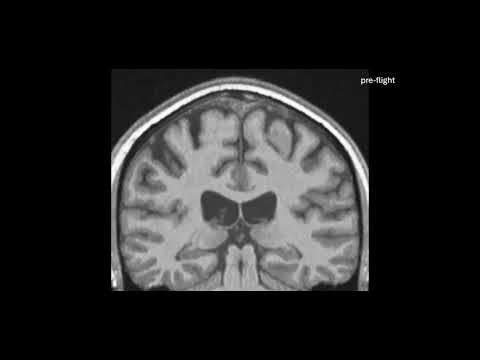

Following a stint in space as short as a few weeks, astronauts can develop measurable changes in the very shape of their brains. For longer stretches of space travel, the alterations can linger for at least six months.

That’s not especially problematic, but it does alter how the brain sits inside the skull. Previous research has shown that the center of mass of astronauts’ brains shifts upward in their skulls after spaceflight, compared to measurements taken before spaceflight.

Their detailed measurements showed that the brain shifts up and back in the skull during spaceflight, and also tilts backwards a little bit too, a tiny, subtle roll, consistent with the findings of previous studies.

However, the brain shifted in other ways, too; not uniformly all over, but with different regions changing in different directions, in a way that can’t be attributed to the movement of the entire brain.

That suggests that the very shape of the brain changes. The most pronounced shifts were observed in longer spaceflights – the brains of astronauts who spent a year in space could change by as much as two to three millimeters.